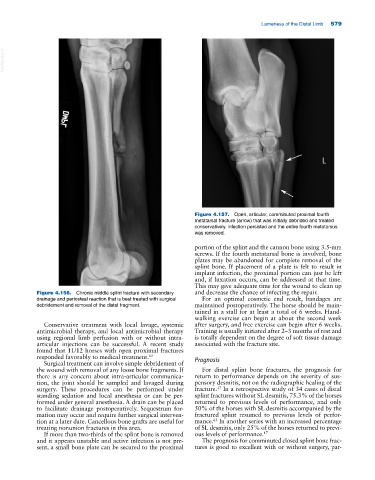

Figure 4.157. Open, articular, comminuted proximal fourth

metatarsal fracture (arrow) that was initially debrided and treated

conservatively. Infection persisted and the entire fourth metatarsus

was removed.